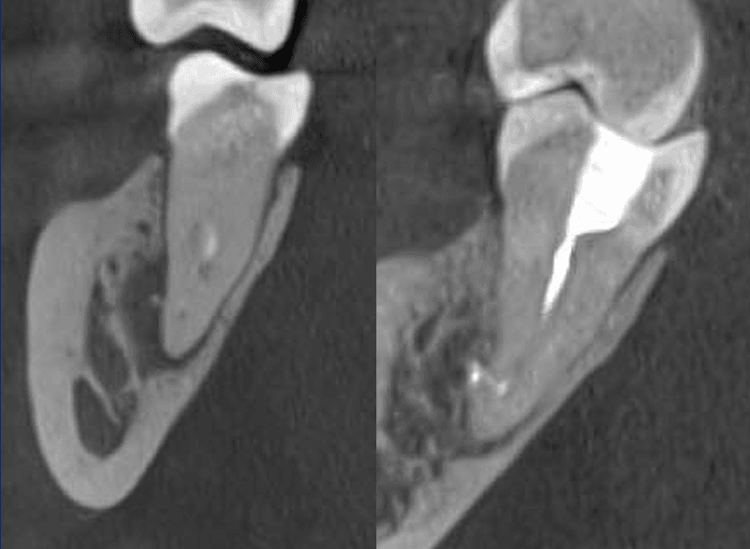

Пациент обратился с жалобами на боль при накусывании на нижний жевательный зуб. Чтобы точно понять причину, мы провели компьютерную томографию (КЛКТ) и обнаружили обширное воспаление костной ткани под корнями зуба, диаметром до 7 мм.

Результат через 8 месяцев:

- полное восстановление костной ткани вокруг корней

- исчезновение боли при жевании

- зуб сохранён и функционирует как здоровый